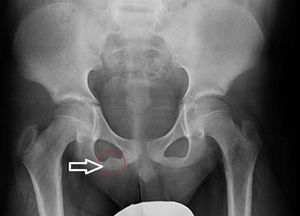

En la radiografía AP de pelvis (fig. 1) evidenció la SIP derecha aumentada de tamaño con pequeñas irregularidades de aspecto seudotumoral. En la RM (fig. 2) una imagen asimétrica e irregular, en «puente fibroso», que afecta a la sindesmosis isquiopubiana derecha (T1) y señal hiperintensa con edema de partes blandas asociado en secuencias T2 y STIR. Todo ello compatible con el diagnóstico de «osteocondritis de Van Neck-Odelberg».

En la radiología simple es habitual el aumento de la sincondrosis con áreas radiolúcidas y osteolíticas. Los hallazgos típicos de la RM incluyen cambios en la médula ósea y edema de partes blandas perilesionales2–4.

La apariencia seudotumoral en la radiología puede confundirse con fracturas de estrés, proceso infeccioso o tumoral1–5. La ausencia de fiebre y la normalidad en las pruebas analíticas nos facilitarán el diagnóstico diferencial1.